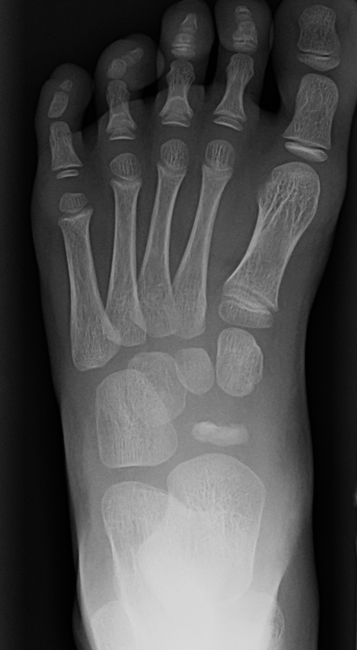

Muller-Weiss disease

Definition

Spontaneous osteonecrosis of the navicular